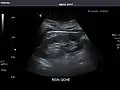

Abdominal Ultrasound (Full Exam)

STRUCTURED REPORT

(Technique: Transabdominal ultrasonography; Device: Toshiba Aplio XG)

Kidneys: Right and left kidneys measure 11.5 cm and 12 cm in length respectively. No hydronephrosis. Small left lower pole kidney cyst.

IMPRESSION:

Normal abdominal ultrasound.

Right kidney